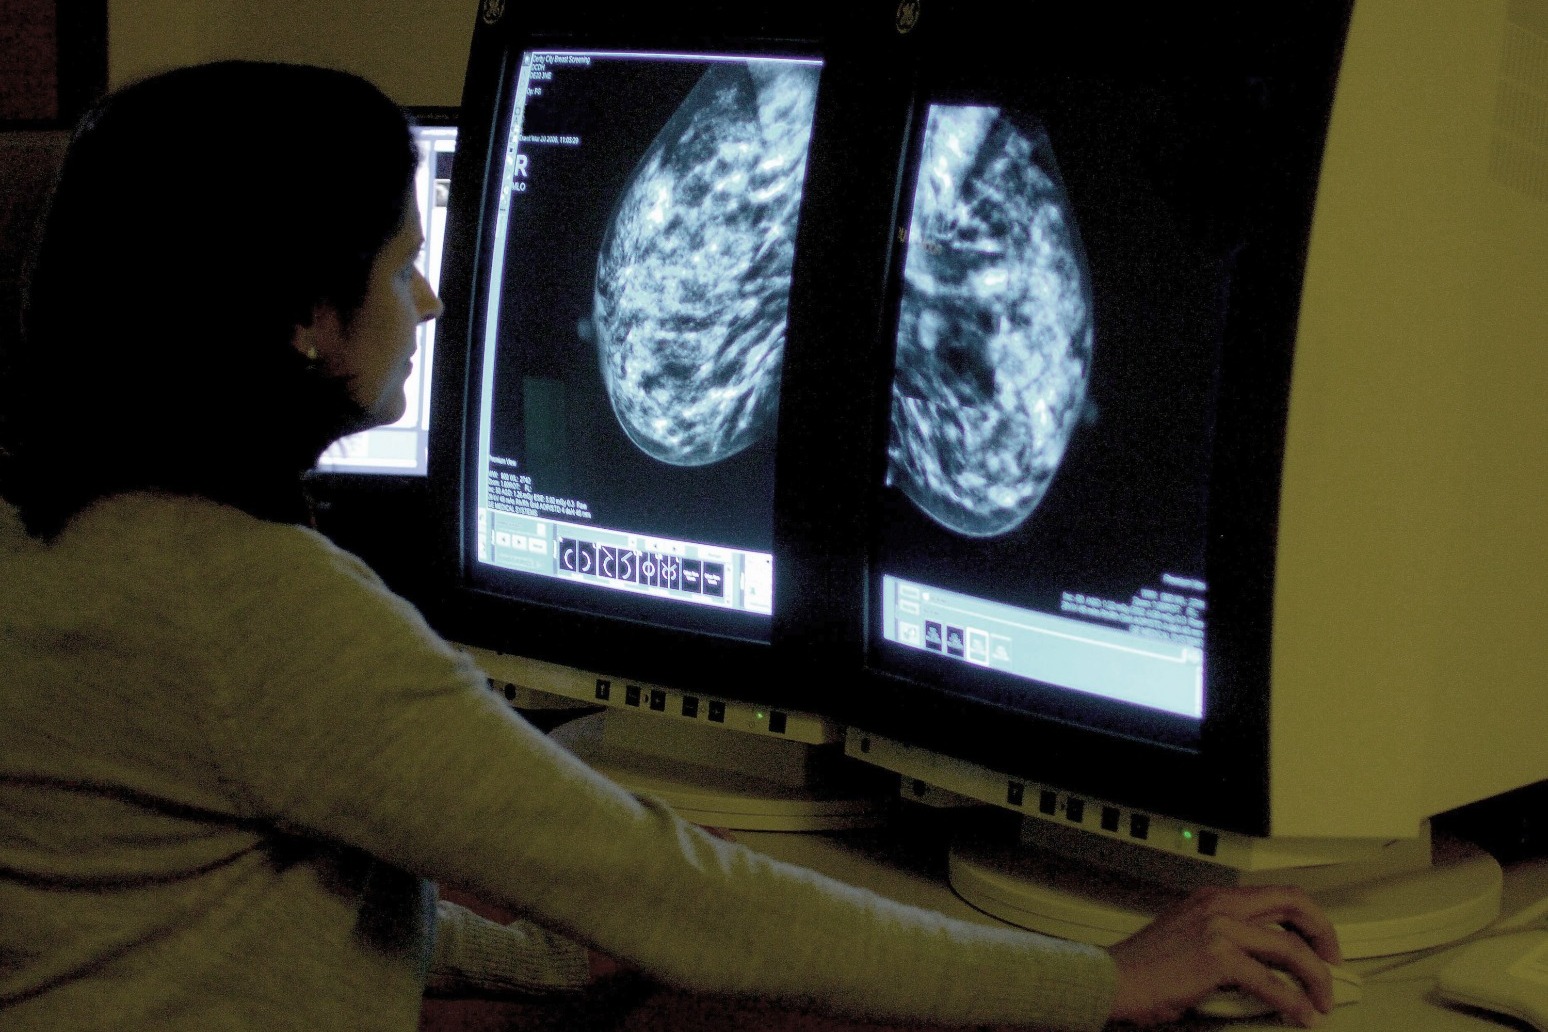

At the appointment, two X-rays are taken of each breast to look for signs of cancer.

Researchers in Australia developed an AI algorithm based on mammogram images from 49,196 women enrolled on the Lifepool cohort registry, an Australian breast cancer research initiative.

“We developed and tested a deep learning algorithm for cardiovascular risk prediction based on routine mammography images.”